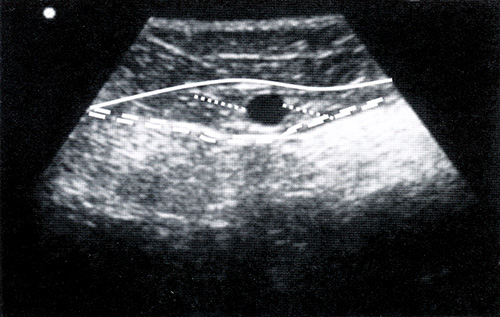

Флебография.

Это метод, при котором вены исследуются рентгенологическим способом с помощью их искусственного контрастирования.

Диагностика варикоза

Флебография используется для исследования структуры и функции вен, оценок венозного кровотока и кровообращения, а также для того, чтобы диагностировать патологические состояния венозного кровотока и т.п.